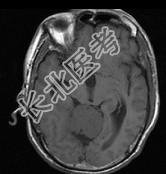

单项选择题男,61岁, 头晕头痛伴行走不稳1月余,请根据所提供图像, 选择最可能的诊断是 ( )

A、淋巴瘤

B、转移瘤

C、胶质瘤

D、髓母细胞瘤

E、(天幕切迹缘)脑膜瘤